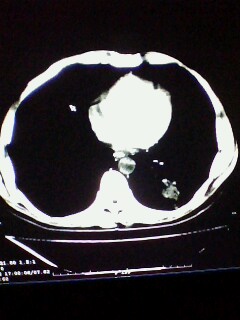

标题: CT28315:咳嗽咳痰咯血半月并胸痛 [打印本页]

标题: CT28315:咳嗽咳痰咯血半月并胸痛

左下肺肿块影,深分叶,考虑肺癌。

不排除左肺下叶周围型肺癌可能!建议穿刺活检!

考虑左肺下叶周围型肺癌并阻塞性肺炎。